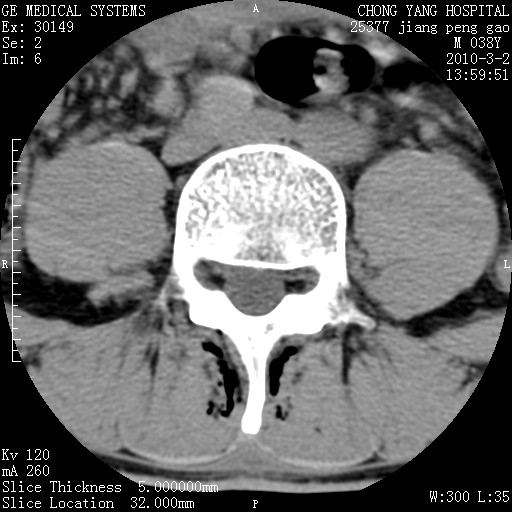

标题: CT24887:M38Y 反复腰痛 无外伤史 未做针灸 竖脊肌为何积气 [打印本页]

标题: CT24887:M38Y 反复腰痛 无外伤史 未做针灸 竖脊肌为何积气

退变,轻度增生/间盘膨出、l5椎后缘软骨结节。

肌间隙积气过多也为退变表现。